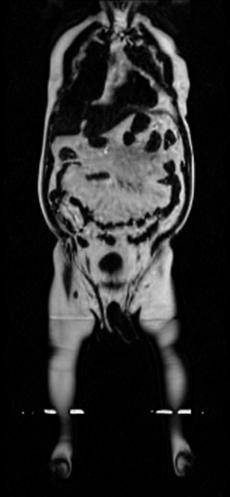

Our results unequivocally highlight the superior performance of X-Diffusion in terms of both qualitative and quantitative metrics. Representative MRI volumes generated by our pipeline, when juxtaposed with ground-truth images, showcased remarkable similarity, with even intricate physiological features like tumor information, spine curvature, and fat distribution being accurately captured.

Notably, X-Diffusion achieves sota dB for a few input slices while baselines require more than 60 input slices to achieve similar performance (Figure 7). The margin is more than 12 dB PSNR for the 1-slice input in both the BRATS and the UK Biobank benchmarks (see Table 1 and Figure 6). For reference, two randomly sampled MRIs from the UK Biobank would have a PSNR of 15.95 dB 0.36 (on 4800 randomly sampled examples). The slices from 3D reconstructed volumes at varying depths and axis of rotation visually match the ground truths (see Figures 5 and Figure 4). We also plot the error map (Figure 4) of such X-Diffusion generations to highlight the differences with the ground truth MRIs.

UK Biobank. A more comprehensive dataset of 48,384 full-body MRIs from more than 500,000 volunteers[67]. UK Biobank MRIs are resampled to be isotropic and cropped to a consistent resolution (501 160 224). 48,384 whole-body MRIs are paired with antero-posterior (AP) DXA scans of the same subjects. These Dixon MRIs do not come stitched, the scans are scanned axially and there is a disparity in the bias field effect (a common artifact of MRI machines) which is strongest at the knee region. These Dixon MRI patches could not be stitched seamlessly with our current pipeline. These artifacts appear on all scans of the UKBiobank that we stitch. Therefore, the X-Diffusion trained on this data will recreate these artifacts regardless of input. The same pattern is present on all samples in the dataset for a fixed depth, while different depth indices will have different fixed patterns. We made sure there was a coherence split, such that each patient was in a unique set. We will publish the unique IDs used for train-validation-testing to confirm there is no leakage, nor retrieval of images. Both datasets are pre-processed to ensure compatibility with the X-Diffusion pipeline and to maximize the fidelity of the generated results. Pre-processing includes data normalization to the range [0,1], conversion to fit the RGB channel expected from the pre-trained diffusion model via replicating the grayscale to each channel, and padding to fit network input resolution 256x256x3.